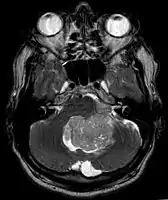

Ependymoma of 4.ventricle in MRI.

Ependymoma of 4.ventricle in MRI. Left without, right with contrast-enhancement.